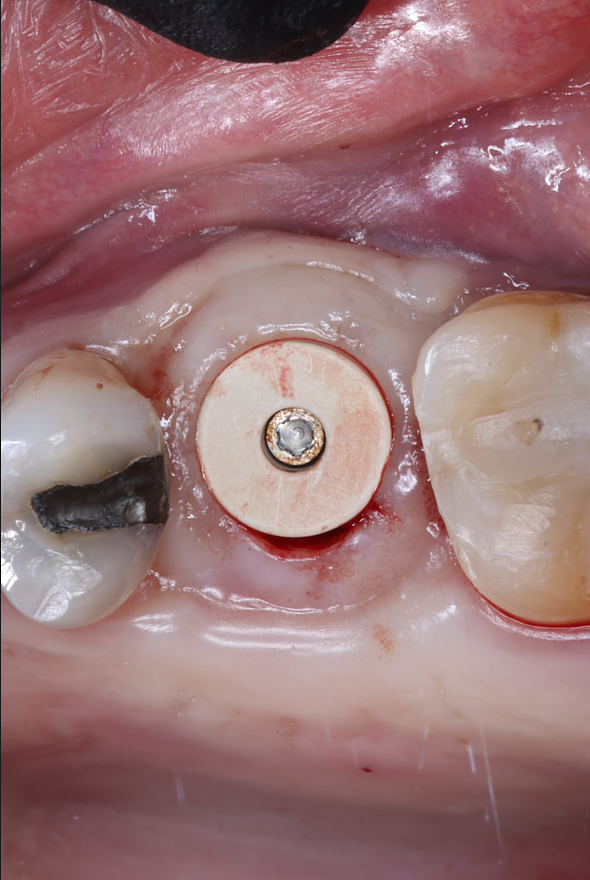

Today, we placed the implant, scanned for the final restoration, just like teaches us to do, and I placed a Neodent healing abutment.

Couple things about this case, I chose to do a tissue punch because the width of the ridge and the amount of attached tissue present. When we use the PTFE membrane for socket preservation, we ultimately grow nice, thick attached tissue, and this is a perfect example of that. I probably only do one or two tissue punches a year.

Notice in the final pictures, the amount of attached tissue is greater around the implant that it is around the natural teeth. Bone is obviously important for implants, but attached tissue will determine how long they last and how healthy they stay.